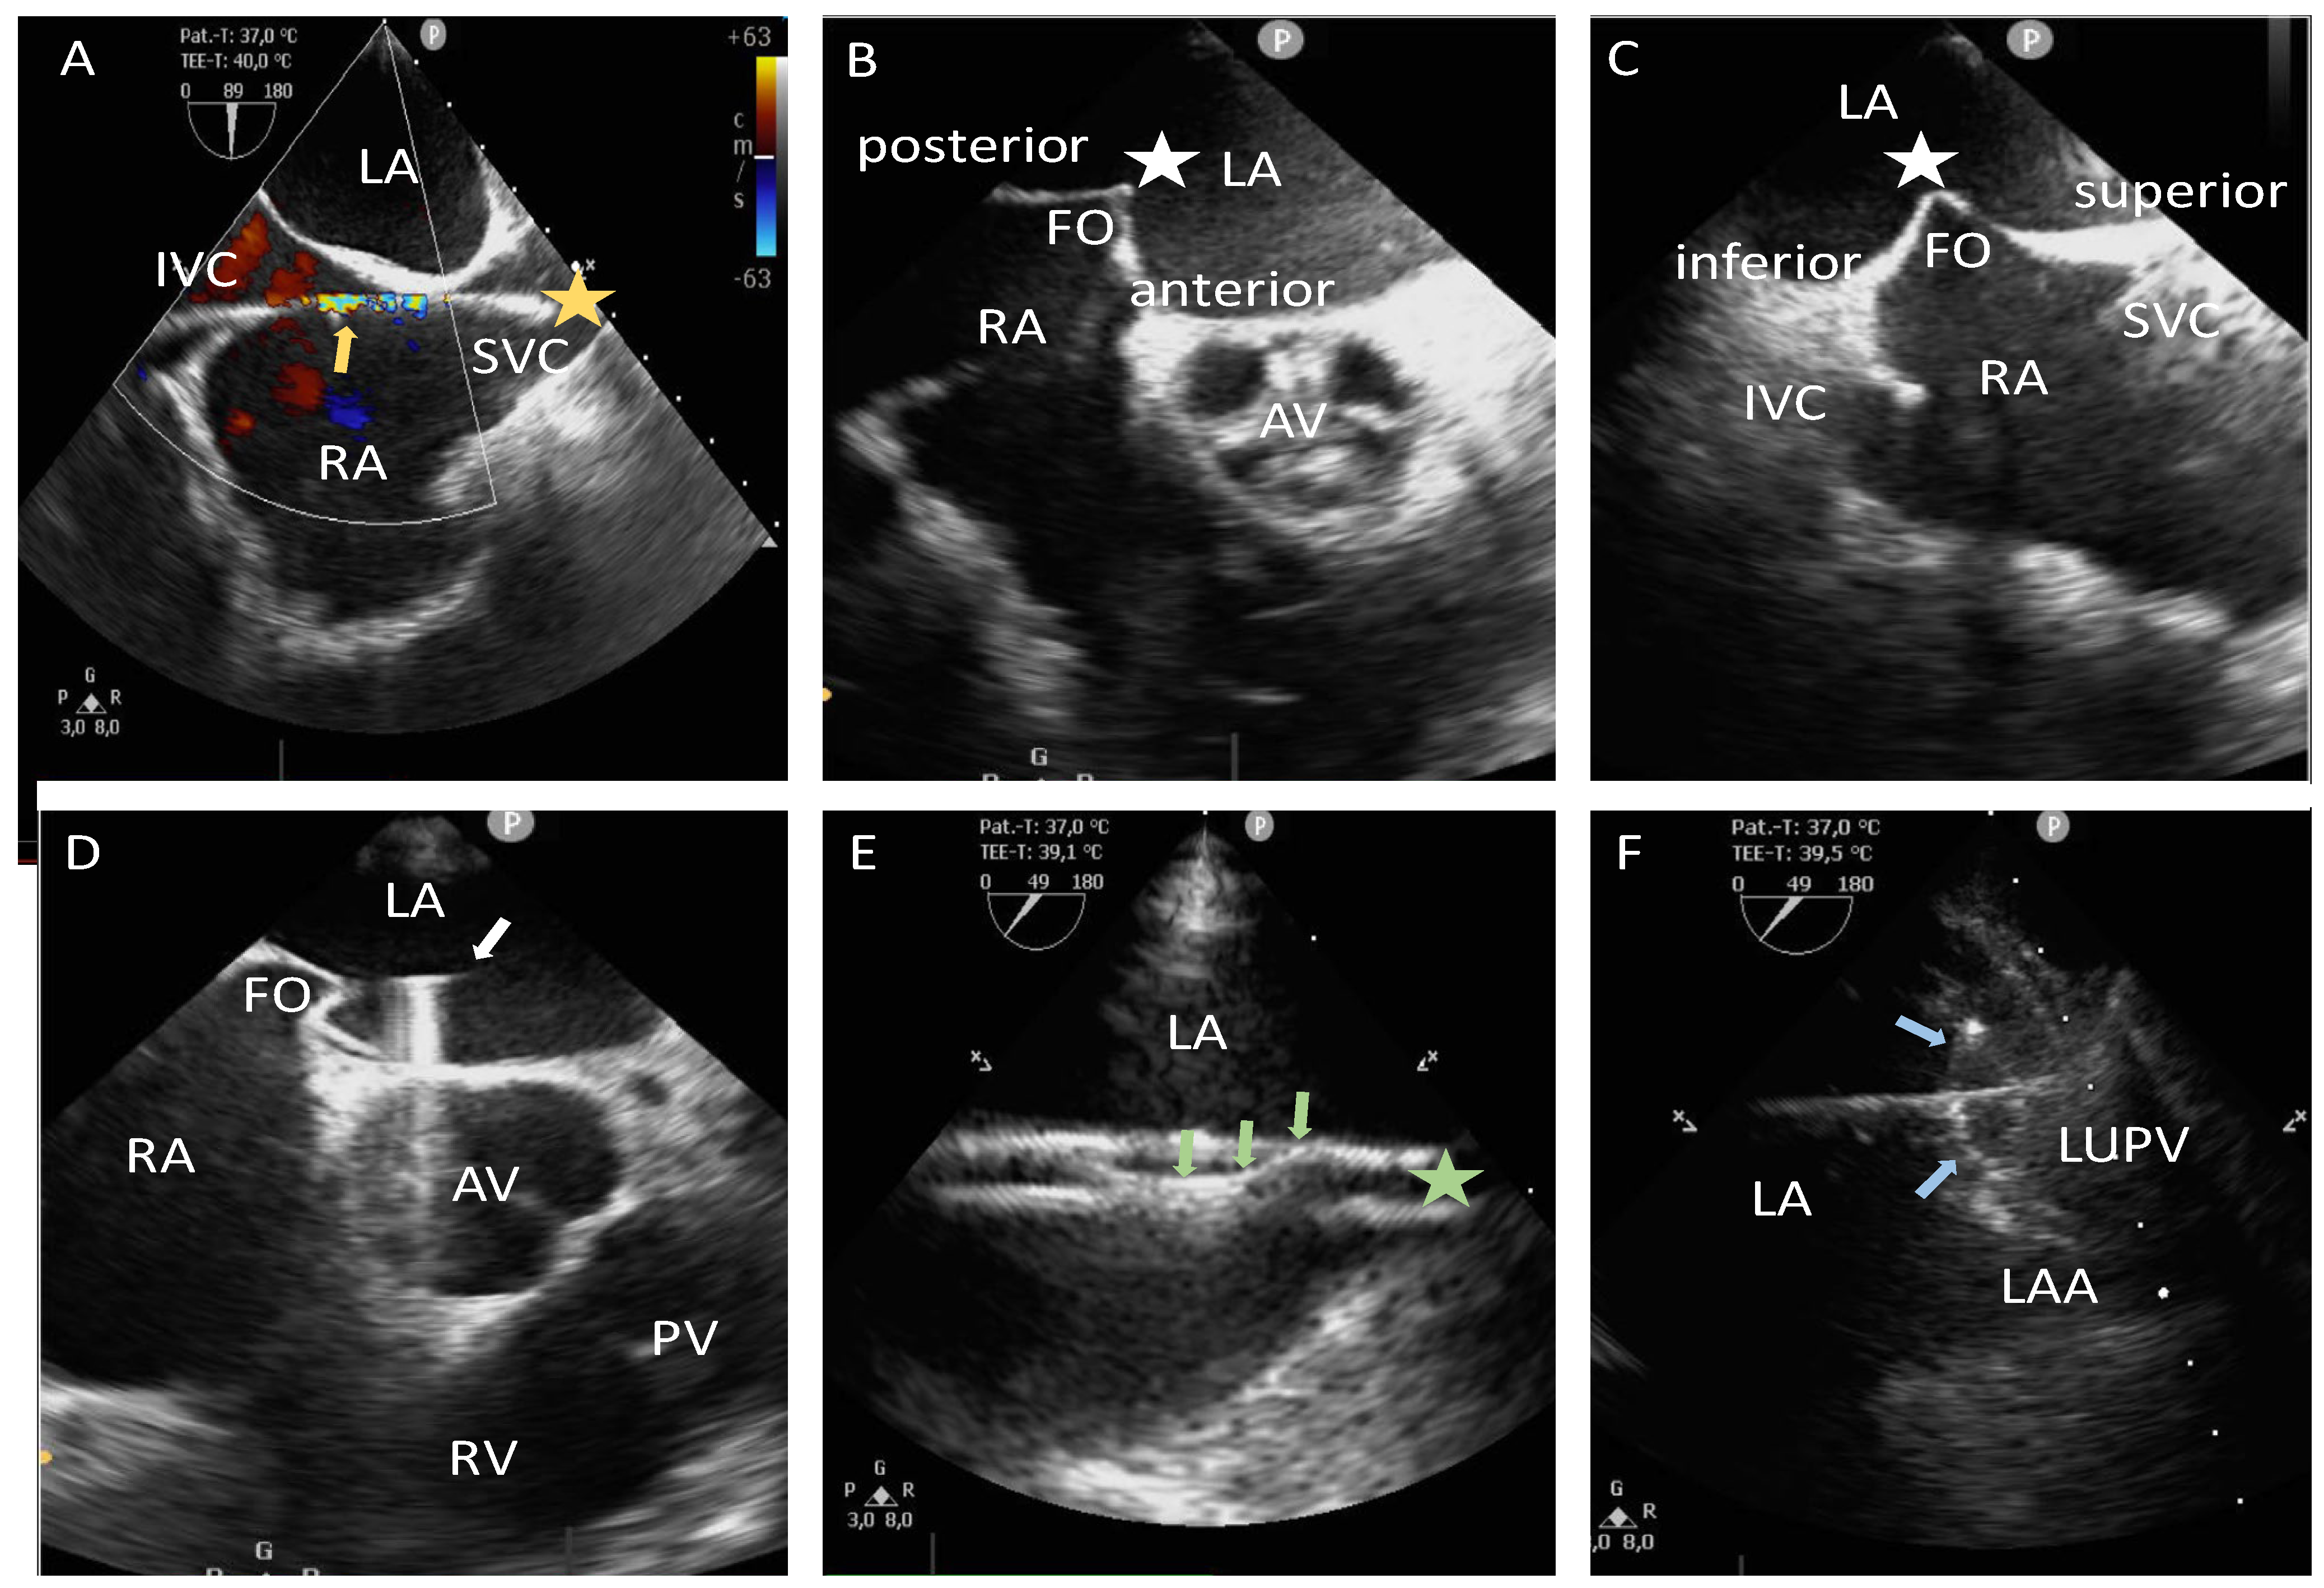

2.3. Zero-Fluoroscopy/Near-Zero-Fluoroscopy Procedure Steps (Zero-Fluro/Near-Zero-Fluoro Group)